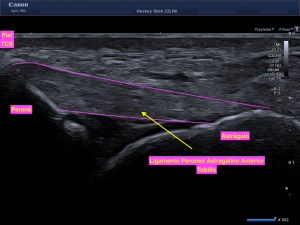

La radiografía revela aumento de las partes y se refrenda en la ecografía como puedes ver en la imagen aunque aún no hay afectación en el hueso en el caso que te presento hoy.

Ecografícamente y debido a su levedad, en el caso de hoy solo observamos cambios en las partes blandas de la cara lateral de la cabeza del quinto metatarsiano, este tejido se muestra heterogéneo, la cortical del hueso ligeramente prominente sin afectación de la misma.